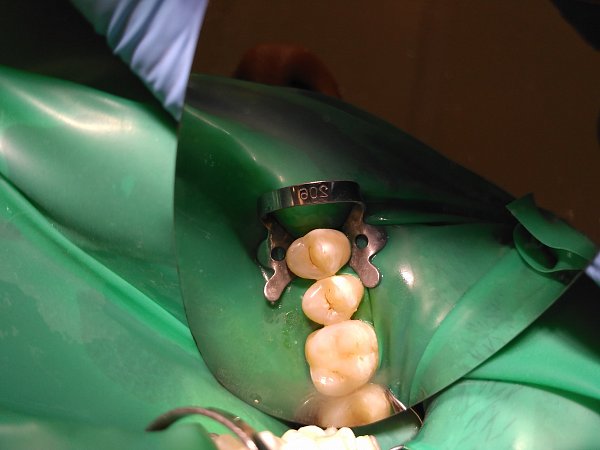

Пациент обратился с жалобами на кариес зубов.

Исходное состояние: Зубы под реставрациями неудовлетворяющими клиническим требованиям

Выполнена реставрация накладками из прессованной керамики.